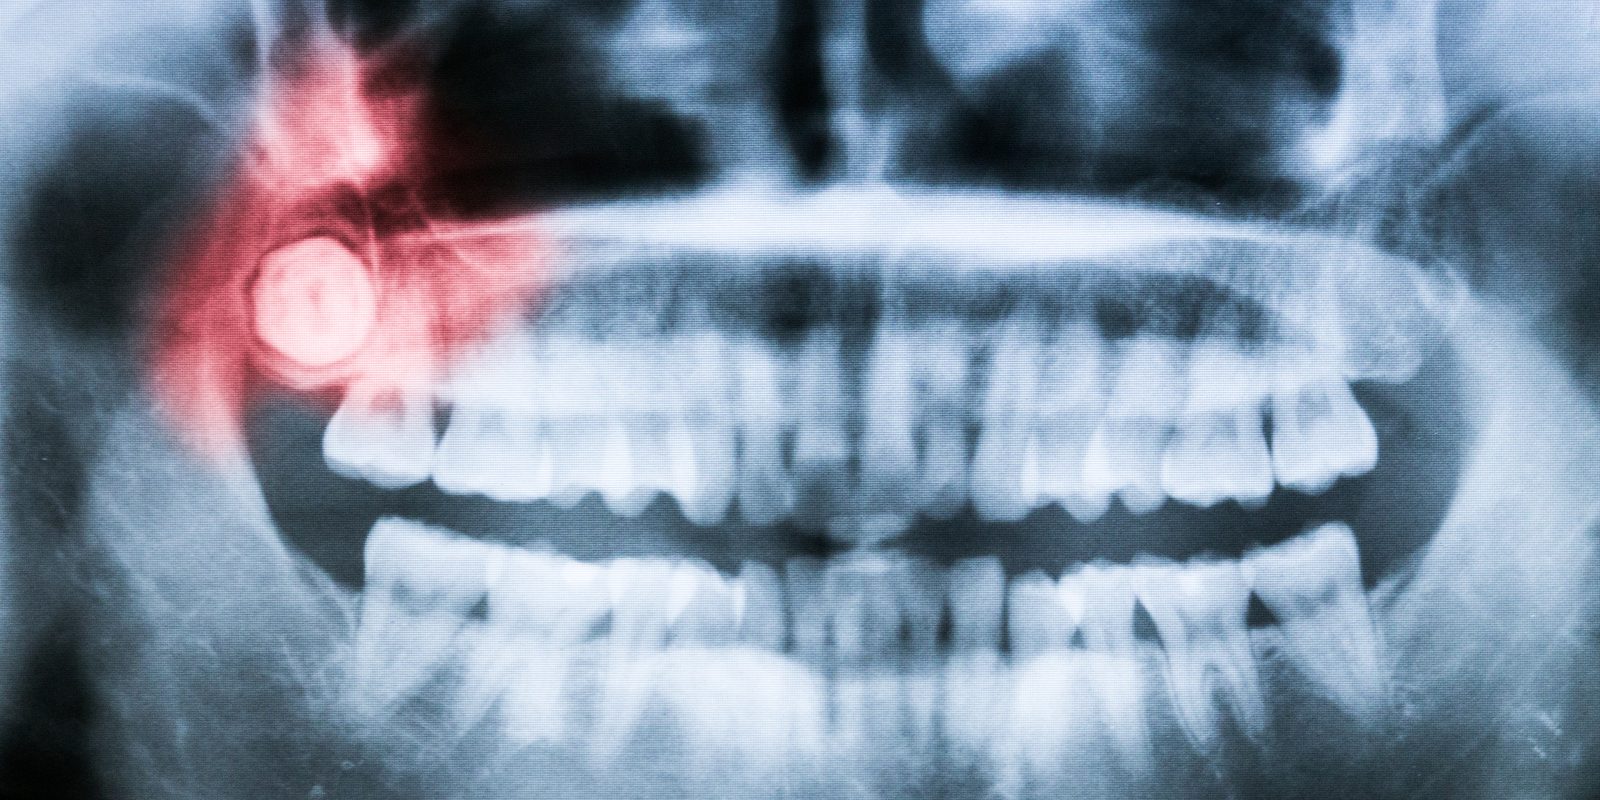

Wisdom teeth impaction can take several forms. The most common, referred to as mesioangular impaction, is when the tooth is angled towards the front of your mouth. The second most common is referred to as vertical impaction, and this occurs when the tooth does not emerge through the gumline. This can be one of the more confusing impactions for patient’s experiencing pain, because the tooth is not visible.

Less common forms of impaction are when the tooth is angled backwards (distoangular impaction) and horizontal impaction, which occurs when the tooth rotates a full 90 degrees and is growing into the roots of the second molar.